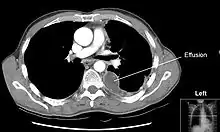

Порожнина плеври — вузька замкнена щілина, у якій є невелика кількість серозної рідини, що зволожує листки плеври. У місцях переходу реберної плеври у діафрагмальну і медіастинальну, утворюються синуси (тут легень немає): реберно-діафрагмальний, діафрагмо-медіастинальний і реберно-медіастинальний.